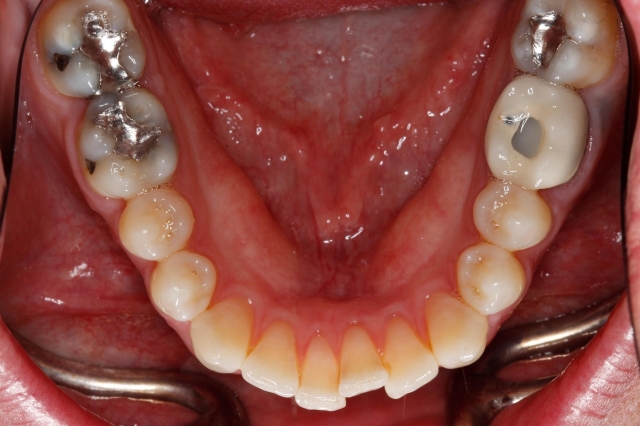

The best way to see everything, including the second molars, is to have the patient open really wide.

I work at getting my framing and focus right while asking the patient to simply “open.” Because it takes a few seconds to get this just right, I don’t have the patient open as big as I need them to until the very last second. Right before I take the shot, I hit the patient with this line: “Open your biggest big!” and I snap quickly. You’ll get a surprising amount of additional opening with this little gem.